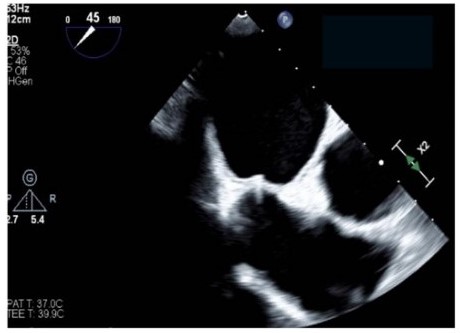

Stroke prevention with oral anticoagulants is one of the main pillars in atrial fibrillation (AF) therapy. However, as a significant proportion of patients have contraindications to their usage, left atrial appendage closure (LAAC) is an established alternative in patients with nonvalvular AF.1 Nonetheless, the procedural workflow for closure device delivery to the left atrial appendage (LAA) is rather complex, including several guidewire and sheath exchanges. Safe puncture of the interatrial septum is critical, and most centers use mechanical puncture with the Brockenbrough (BRK) needle (Medtronic) as their standard of care. There is a novel multipurpose radiofrequency wire system that includes a radiofrequency wire for transseptal puncture and a shapeable dilator that fits within the closure device delivery sheath. Consequently, transseptal puncture and closure device deployment can be performed within the same sheath, and both wire and dilator are removed after left atrial access is achieved (Figure A and B).